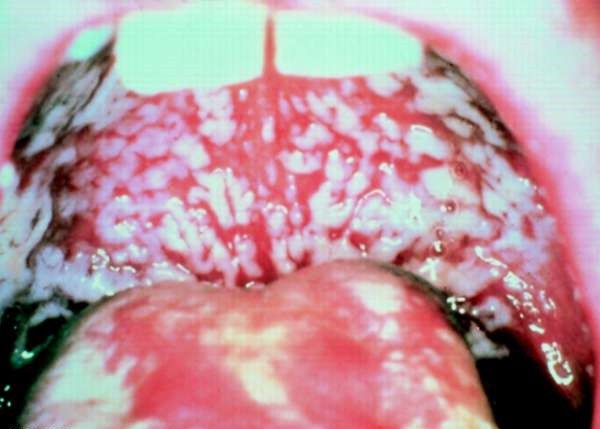

Фото

Острый псевдомембранозный

Наиболее распространенная форма заболевания, которую в народе часто называют «молочницей» из-за сходства по внешним признакам серо-белого налета с творогом или молоком. Чаще всего болезнь поражает маленьких детей, лечение у которых происходит достаточно легко, если своевременно его начать.

При отсутствии должного уровня санации ротовой полости увеличивается площадь поражения, белесые бляшки сливаются между собой, а при их удалении открывается эрозированная поверхность слизистой оболочки. Иногда творожистого налета такое количество, что он покрывается всю спинку языка, придавая ей неестественный цвет. Если процесс затрагивает глубокие слои мягких тканей, то пораженные участки принимают бурый окрас и кровоточат.